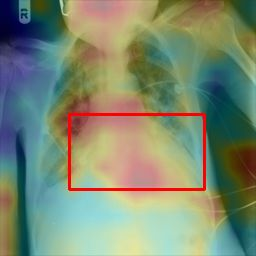

Deployments of artificial intelligence in medical diagnostics mandate not just accuracy and efficacy but also trust, emphasizing the need for explainability in machine decisions. The recent trend in automated medical image diagnostics leans towards the deployment of Transformer-based architectures, credited to their impressive capabilities. Since the self-attention feature of transformers contributes towards identifying crucial regions during the classification process, they enhance the trustability of the methods. However, the complex intricacies of these attention mechanisms may fall short of effectively pinpointing the regions of interest directly influencing AI decisions. Our research endeavors to innovate a unique attention block that underscores the correlation between 'regions' rather than 'pixels'. To address this challenge, we introduce an innovative system grounded in prototype learning, featuring an advanced self-attention mechanism that goes beyond conventional ad-hoc visual explanation techniques by offering comprehensible visual insights. A combined quantitative and qualitative methodological approach was used to demonstrate the effectiveness of the proposed method on the large-scale NIH chest X-ray dataset. Experimental results showed that our proposed method offers a promising direction for explainability, which can lead to the development of more trustable systems, which can facilitate easier and rapid adoption of such technology into routine clinics. The code is available at www.github.com/NUBagcilab/r2r_proto.